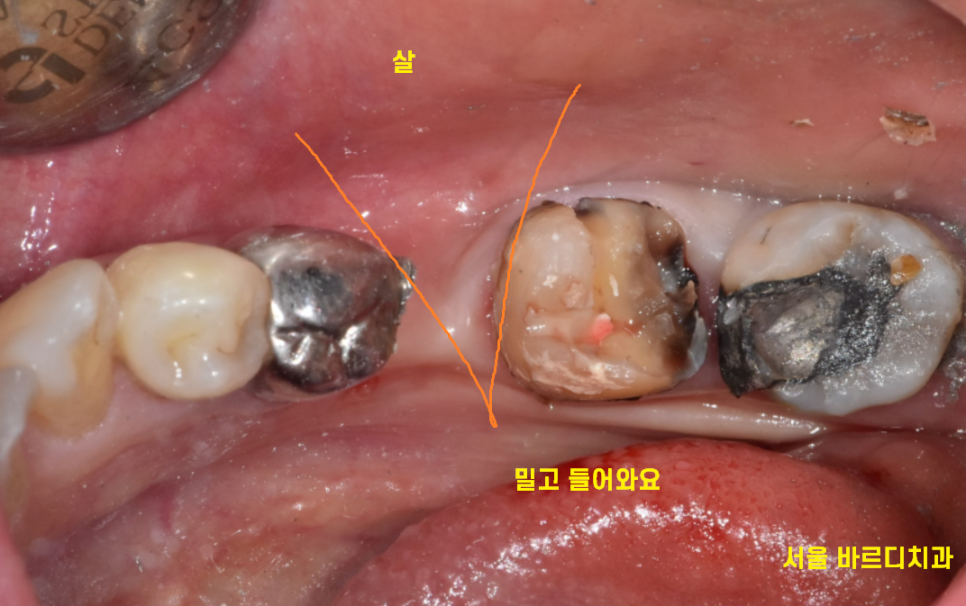

볼을 씹는 이유 중 하나는

살이 밀고 들어와서입니다.

치아가 빠진지 시간이 경과하면

치아가 없는 쪽으로

살이 채워집니다 .

치아가 있던 자리

"공간"이 생기면서

이 곳을 채우기 위해

볼살이 밀고 들어오는 것이죠~

이것은 일시적인 현상입니다.